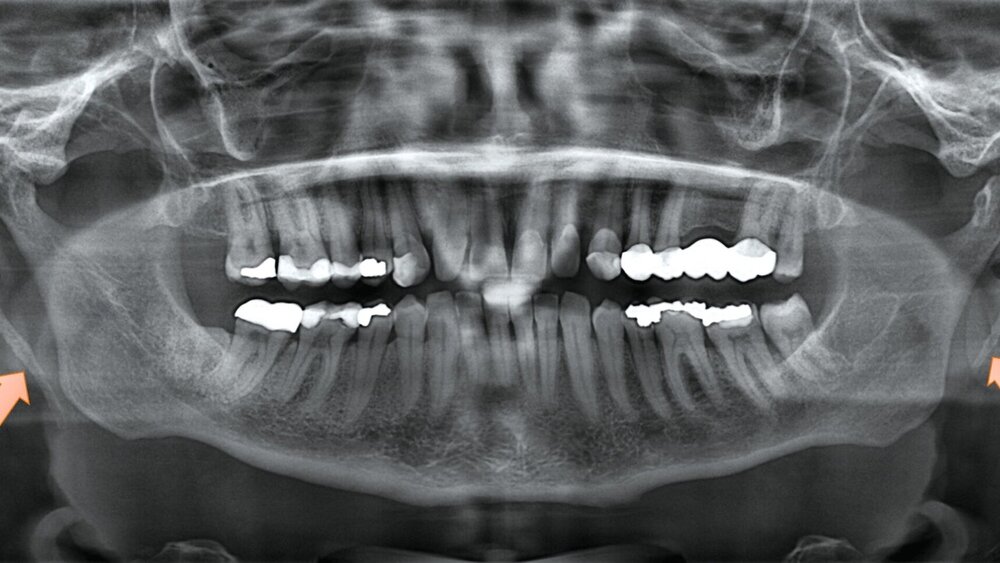

Eine 49-jährige Patientin stellte sich vor, nachdem ihr Hauszahnarzt im Rahmen einer Routineuntersuchung ein Orthopantomogramm (OPG) angefertigt hatte. Dabei war zufällig eine beidseitige Verlängerung des Processus styloideus aufgefallen, dabei auf der rechten Seite deutlich ausgeprägter (Abbildung 1).

Die klinische Untersuchung ergab keine Hinweise auf Sensibilitätsstörungen, eine Fazialisparese oder Hirnnervenausfälle. Allerdings war die Palpation des rechten Kieferwinkels schmerzhaft, insbesondere bei der intraoralen Untersuchung der Tonsillenloge. Eine mechanische Provokation durch Kopfdrehung und Palpation verstärkte die Beschwerden. Die prothetisch versorgten Zähne zeigten keine pathologischen Befunde. Zur weiteren Diagnostik wurde eine Digitale Volumentomografie (DVT) mit 3D-Rekonstruktion durchgeführt. Diese bestätigte die im OPG vermutete Diagnose eines beidseitig elongierten Processus styloideus, mit einer stärkeren Ausprägung auf der rechten Seite (Abbildung 2).

Die Diagnostik des Eagle-Syndroms basiert auf einer Kombination aus Anamnese, klinischer Untersuchung und bildgebenden Verfahren. Als Erstuntersuchung ist ein OPG geeignet, liefert jedoch keine detaillierten Informationen über die räumliche Lage des verlängerten Processus styloideus. Daher gilt die dreidimensionale Bildgebung (CT oder DVT) als Goldstandard, um die exakte Länge und die Beziehung zu den angrenzenden Strukturen zu bestimmen [Mortellaro et al., 2002]. Differenzialdiagnostisch müssen Kiefergelenkpathologien, eine Trigeminusneuralgie und psychosomatische Ursachen ausgeschlossen werden, was jedoch durch eine bildgebende Diagnostik zuverlässig möglich ist [Kozakovičová et al., 2023].